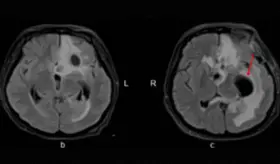

Los episodios de hemorragia cerebelosa, pérdida de visión y alteraciones severas del estado mental, junto con lesiones desmielinizantes progresivas. A pesar de tratamientos como esteroides, timectomía y plasmaféresis, la paciente continuó deteriorándose.

Los estudios de neuroimagen revelaron vasculitis cerebral como complicación tardía, manifestándose con áreas de realce de contraste en sustancia blanca, edema vasogénico e infartos múltiples.

La enfermedad se relaciona con fallas del sistema inmunológico y, en este caso, podría estar ligada a la miastenia gravis y al timoma previo de la paciente, factores que complicaron el diagnóstico.

Los hallazgos en resonancia magnética mostraron el patrón característico de edema vasogénico en regiones parieto-occipitales bilaterales.